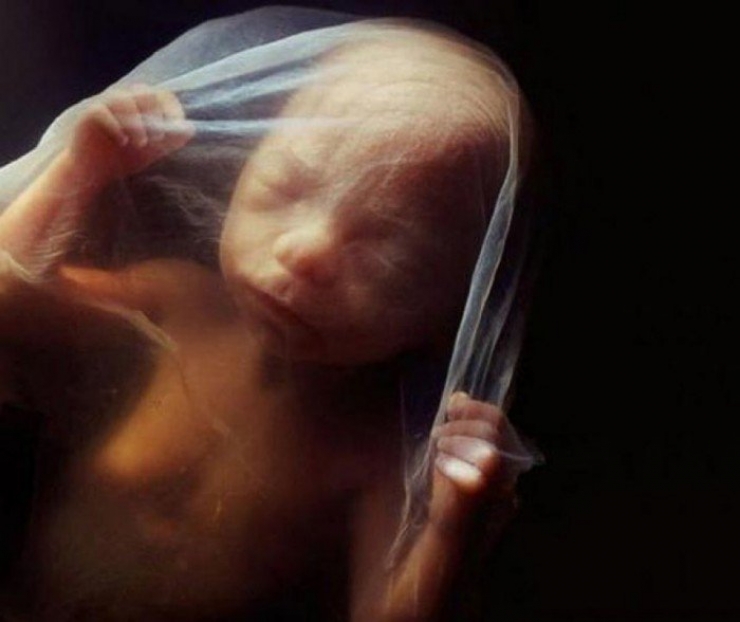

En 1965, le célèbre magazine « LIFE » (disparu aujourd’hui) utilise l’une des photos du photographe en couverture: Celle d’un d’embryon flottant littéralement dans son placenta, raccordé à sa maman via le cordon ombilical.

Le magazine a consacré 16 pages au photographe, expliquant chronologiquement la formation et l’évolution d’un embryon humain...

Quelques semaines plus tard est né le livre « Naître » de Lennart Nilsson.